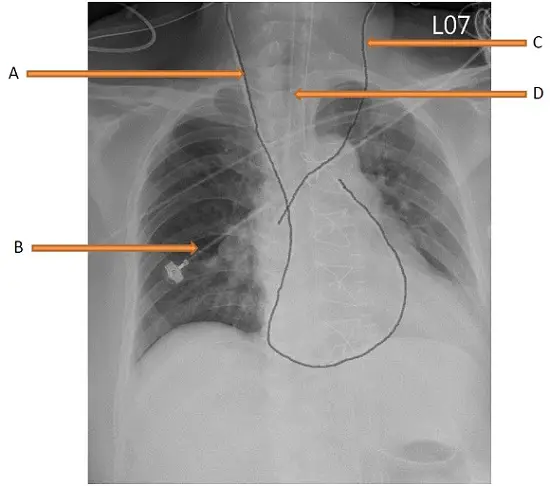

下圖胸部X光檢查中,那一條是中心靜脈壓導管(CVP line)?

- 標示 A (Nasogastric Tube):

- 觀察:此管路從頭頸部向下延伸,沿著脊椎/食道走向垂直下降,並穿過橫膈膜(Diaphragm)進入腹腔/胃部。

- 判斷:這是典型的 鼻胃管(NG tube)。其特徵是路徑筆直且末端位於橫膈膜下方。

- 標示 B (ECG Electrode):

- 觀察:位於右側肺野(Right lung field)上的金屬密度物體,形狀呈圓形或矩形扣狀,且連結著細線。

- 判斷:這是 外部心電圖電極貼片(ECG electrode),貼在患者胸壁皮膚上,並非植入體內的管路。

- 標示 C (Central Venous Catheter / CVP line):

- 觀察:此管路起源於 左側頸部(病人的左側,影像的右側),沿著縱膈腔向下走行,並跨越中線進入上腔靜脈(SVC)或右心房區域。影像中可見該導管在心臟陰影處形成迴圈(loop),這通常是肺動脈導管(Swan-Ganz catheter)的特徵。

- 判斷:雖然 Swan-Ganz 導管主要用於測量肺動脈壓,但它本身是由中心靜脈置入(如經由左側內頸靜脈或鎖骨下靜脈),且導管近端開口(Proximal port)位於右心房,可用於測量 中心靜脈壓(CVP)。在考題選項中,這是唯一符合「中心靜脈管路」特徵的選項。

- 標示 D (Endotracheal Tube):

- 觀察:位於頸部正中央氣管內的管狀結構,其末端(Tip)位於氣管隆突(Carina)上方約 3-5 公分處。

- 判斷:這是 氣管內管(Endotracheal Tube, ETT),用於維持呼吸道暢通。

- A:由影像可見管路延伸至橫膈膜下方,為 鼻胃管(NG tube),非 CVP line。

- B:位於胸壁外的金屬扣件,為 心電圖電極(ECG electrode),非管路。

- C:由左頸靜脈或鎖骨下靜脈進入,末端位於心臟/上腔靜脈區域,為 中心靜脈導管(CVP line / Swan-Ganz)。此為正確答案。

- D:位於氣管內,為 氣管內管(ETT),非 CVP line。

正確答案:C

題目詢問「哪一條是中心靜脈壓導管(CVP line)」。

- C 指向的管路是經由靜脈系統(左側內頸靜脈 Left IJV 或鎖骨下靜脈 Left Subclavian Vein)置入。雖然影像顯示的可能是一條肺動脈導管(因其在心臟內繞圈進入肺動脈),但肺動脈導管必須經由中心靜脈置放,且具備測量 CVP 的功能(Proximal port)。在四個選項中,只有 C 是血管內導管,符合 CVP line 的定義與位置。